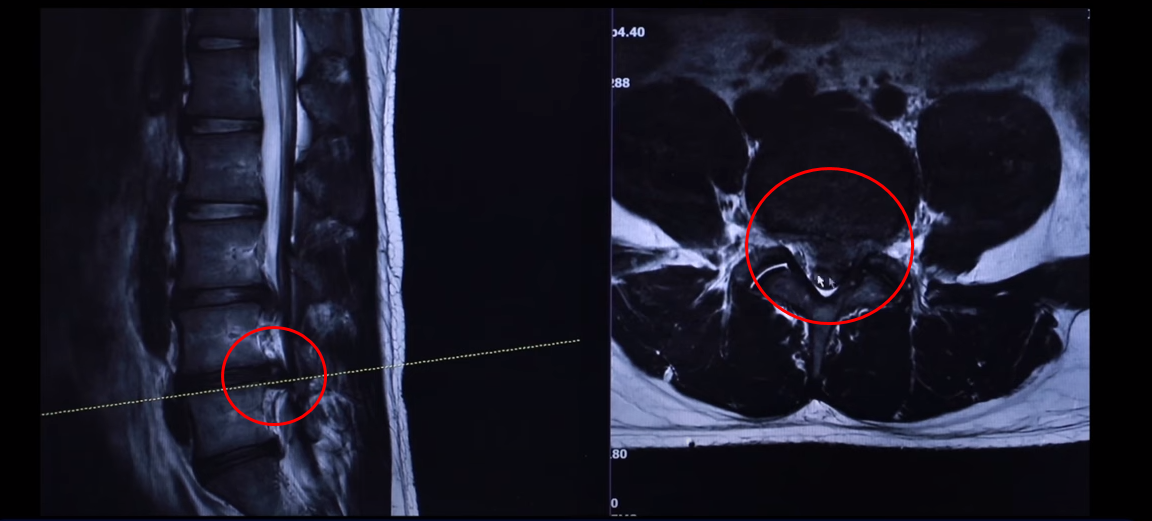

여기 24세 남자 환자분 MRI 보도록 하겠습니다. 옆에서 보는 MRI 보시다시피 어마어마하게 지금 심하게 터져 있습니다. 일반인이 보셔도 아실 정도로 두 마디가 아주 심하게 터졌고 여기도 약간 밀려 나와 있습니다.

단면을 한번 보도록 하겠습니다. 여기를 잘라서 본 단면인데요. 왼쪽으로 많이 밀려 나와 있죠? 이 한마디만 해도 파열돼서 상당히 많이 밀려 나온 겁니다. 왼쪽 다리가 저리고 아플 수 있습니다.

그 다음 마디 4번, 5번 보시면 보시다시피 아예 신경이 거의 보이지 않을 정도로 많이 밀려나왔습니다. 이렇게 심하게 파열된 경우를 보는 건 참 드뭅니다. 거의 신경이 보이지 않을 정도로, 오른쪽에 약간 하얀 부분이 남아 있습니다. 그래서 이 환자분 증상이 왼쪽 다리 증상입니다.